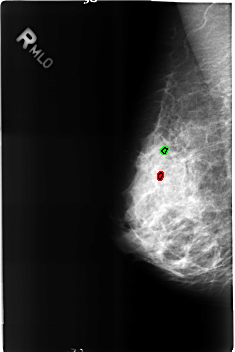

B_3162_1.RIGHT_MLO

FILE: B_3162_1.RIGHT_MLO.OVERLAY

TOTAL_ABNORMALITIES 2

ABNORMALITY 1

LESION_TYPE CALCIFICATION TYPE ROUND_AND_REGULAR-LUCENT_CENTER DISTRIBUTION N/A

ASSESSMENT 2

SUBTLETY 4

PATHOLOGY BENIGN_WITHOUT_CALLBACK

TOTAL_OUTLINES 1

BOUNDARY

ABNORMALITY 2